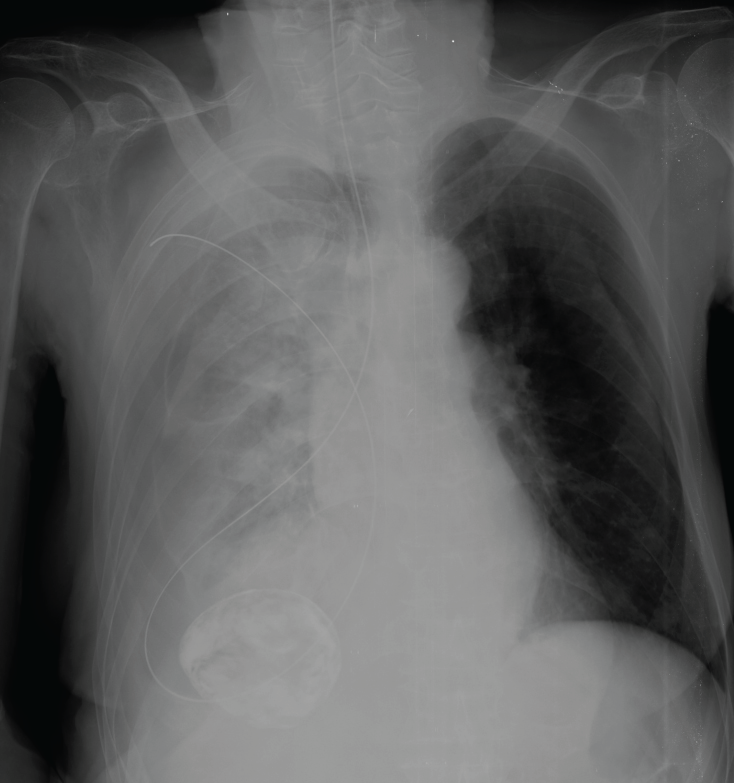

A 75-year-old female patient with past medical history of severe Alzheimer's disease, totally dependent with nasogastric tube feeding (NGT) presented to the emergency department with worsening dyspnea in the past 48 hours. Physical examination revealed on auscultation decreased air entry over the right lung and dullness to percussion. Two days before admission the patient had the NGT changed and a chest X-ray to corroborate position that was checked by one of the junior doctors and discharged to the nursing home. A thoracic bedside ultrasound demonstrated right pleural effusion. A chest radiograph revealed malposition of the NGT in the right pleural space and hydropneumothorax, the NGT was immediately removed without complications and thoracic drainage was inserted obtaining 1200 ml of enteral nutrition (Figure 1, Figure 2, Figure 3 and Figure 4). Her hospital course was satisfactory, and the patient was discharged 7 days later.

Figure 1: Nasogastric tube in the right hemithorax.